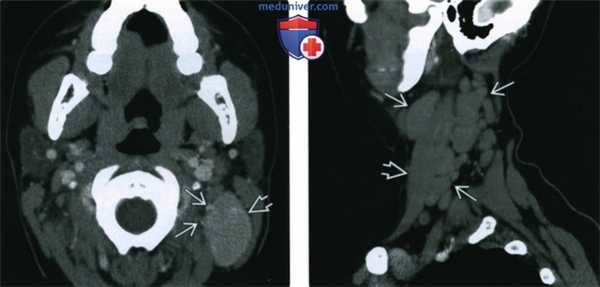

(Слева) КТ с КУ, аксиальная проекция у пациента с единичным пальпируемым образованием на шее, которое равномерно накапливает контраст. Визуализируется крупный лимфоузел, умеренно накапливающий контраст, рядом расположены сосуды. Был поставлен диагноз унифокальной гиалиново-васкулярной формы болезни Кастлемана. Полное излечение достигнуто путем удаления лимфоузла.

(Справа) МРТ Т1ВИ FS с КУ, другой пациент с гиалиново-васкулярной болезнью Кастлемана. Узлы правой яремной цепи однородно накапливают контраст. Узел, расположенный кзади, достигает больших размеров. Признаков воспаления или внекапсулярного распространения нет. (Слева) КТ с КУ, коронарная реконструкция. Крупный, однородный узел В правой яремной цепи, накапливающий контрастное вещество. Также видны мелкие узлы уровня IV и противоположной яремной цепи, которые накапливают контраст менее интенсивно.

(Справа) MPT Т2ВИ FS, коронарная проекция, тот же пациент. Крупный лимфоузел В с равномерным гиперинтенсивным сигналом. Признаков некроза узла или воспаления окружающих тканей нет. Также виден более мелкий, умеренно интенсивный узел.